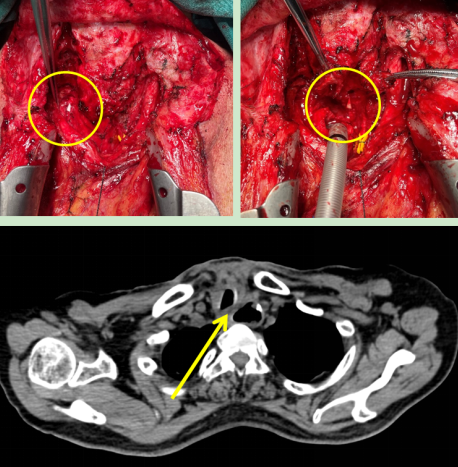

图2:术中情况(左)喉返神经监测仪监测喉返神经,(右)离断气管暴露食管瘘口;

(下)术后CT显示原气管食管间瘘口已修补。

在与患者及家属充分沟通后,胡杨团队为患者行“经颈部及正中开胸气管食管瘘修补术,胸大肌带蒂肌瓣转移成形术”。术中使用喉返神经监测保护喉返神经,使用带蒂胸大肌肌瓣隔绝气管与食管间瘘口。手术顺利完成,术后患者未发生声音嘶哑。

术后第五天,患者突然出现颈部皮下气肿,经检查是因为之前院外手术形成的瘢痕,导致气管缺血坏死,出现气管吻合口瘘。这是多次手术的患者术后可能出现的问题之一,处理极其困难,若处理不当极易造成慢性胸骨感染,甚至威胁生命。胡杨副主任医师立马安排第二次手术,术中使用另一侧带蒂胸大肌肌瓣修补并加固了气管瘘口,术后复查显示气管瘘口成功修补。